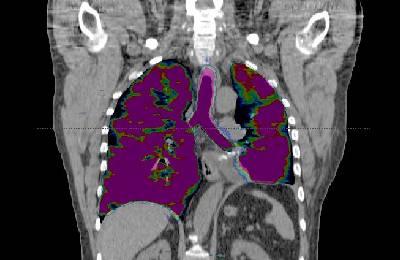

Позитронно-эмиссионная компьютерная томография (ПЭТ-КТ) является высокочувствительным методом диагностики раковых опухолей, поскольку помогает изучить молекулярную структуру раковых клеток.

Этот метод КТ основан на визуализации опухолевых клеток и изучении их метаболизма с помощью радиоактивного фармпрепарата , 18-фтордезоксиглюкозы. Срезы, полученные после введения этого препарата, позволяют создать трехмерную модель опухолевого образования и установить его точную локализацию.

Компьютер накладывает срезы друг на друга, моделируя трехмерное изображение исследуемой области. МРТ позволяет выполнять сканирование срезами от 1 мм в нескольких плоскостях одновременно, что обеспечивает получение снимков высокой четкости.